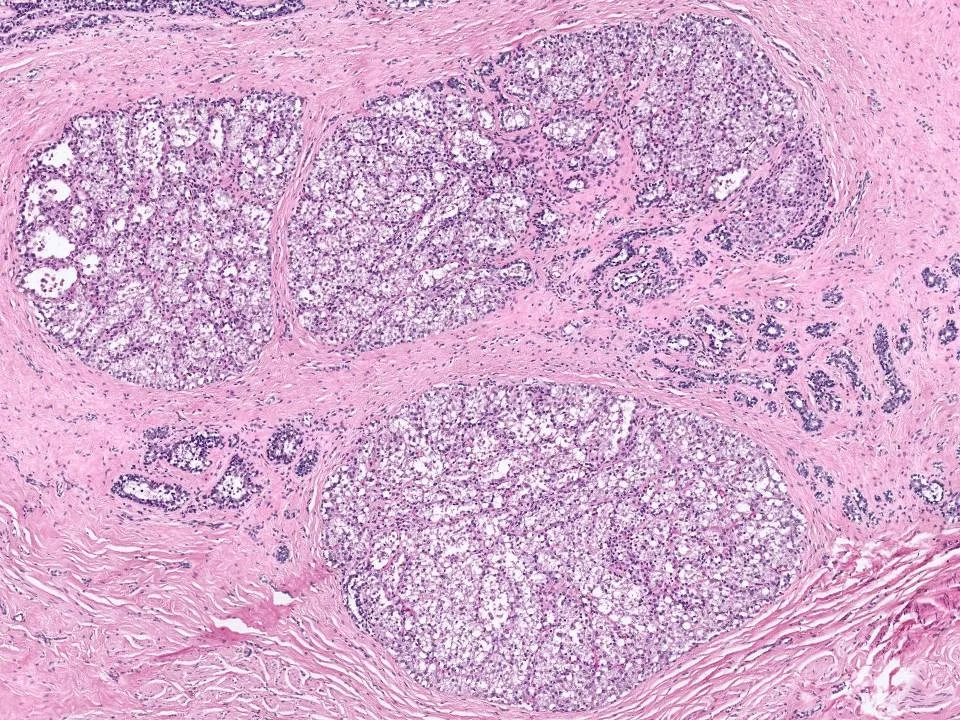

Invasive Lobular Carcinoma, Solid Variant

Variant forms of invasive lobular carcinoma differ from the classical form with regard to architectural and/or cytologic features. In the solid variant, the cells comprising the tumor are cytologically similar to those of the classical form of ILC. However, they differ with regard to growth pattern.

In the solid variant of invasive lobular carcinoma, the tumor cells grow in large confluent sheets with little intervening stroma.

The neoplastic cells of the solid variant of invasive lobular carcinoma show similar cytologic features to the classic type. The cells are small and uniform. Loss of cohesion, which is a feature commonly present in ILC, is demonstrated in this solid area.